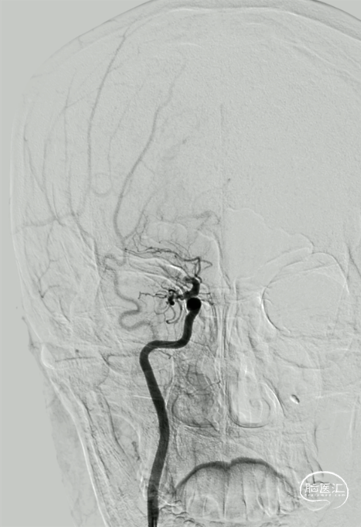

释放Syphonet®取栓支架 5*35mm,造影显示:支架释放效应可疑阳性。

造影:考虑局部血栓可能。

“SWIM”技术取栓,行血栓廓清。

取栓后造影,M1再通,局部狭窄可能,前向血流延迟。

M1局部狭窄,合并小血栓可能。

再次释放Syphonet®取栓支架 5*35mm,造影显示:支架释放效应阳性。

M1局部重度狭窄。